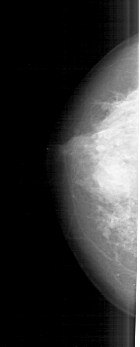

A_1825_1.RIGHT_MLO

RIGHT_MLO LINES 5176 PIXELS_PER_LINE 2716 BITS_PER_PIXEL 12 RESOLUTION 43.5 OVERLAY

FILE: A_1825_1.RIGHT_CC.OVERLAY

TOTAL_ABNORMALITIES 1

ABNORMALITY 1

LESION_TYPE CALCIFICATION TYPE PLEOMORPHIC DISTRIBUTION DIFFUSELY_SCATTERED

ASSESSMENT 5

SUBTLETY 5

PATHOLOGY MALIGNANT

TOTAL_OUTLINES 1

BOUNDARY